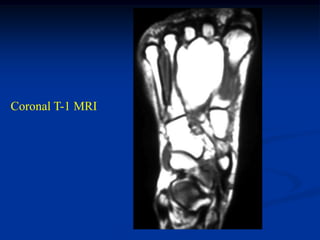

Case #272                  Sagittal T-1 MRI

47 year female with intramuscular lipoma foot

Axial T-1 MRI

Coronal T-1 MRI